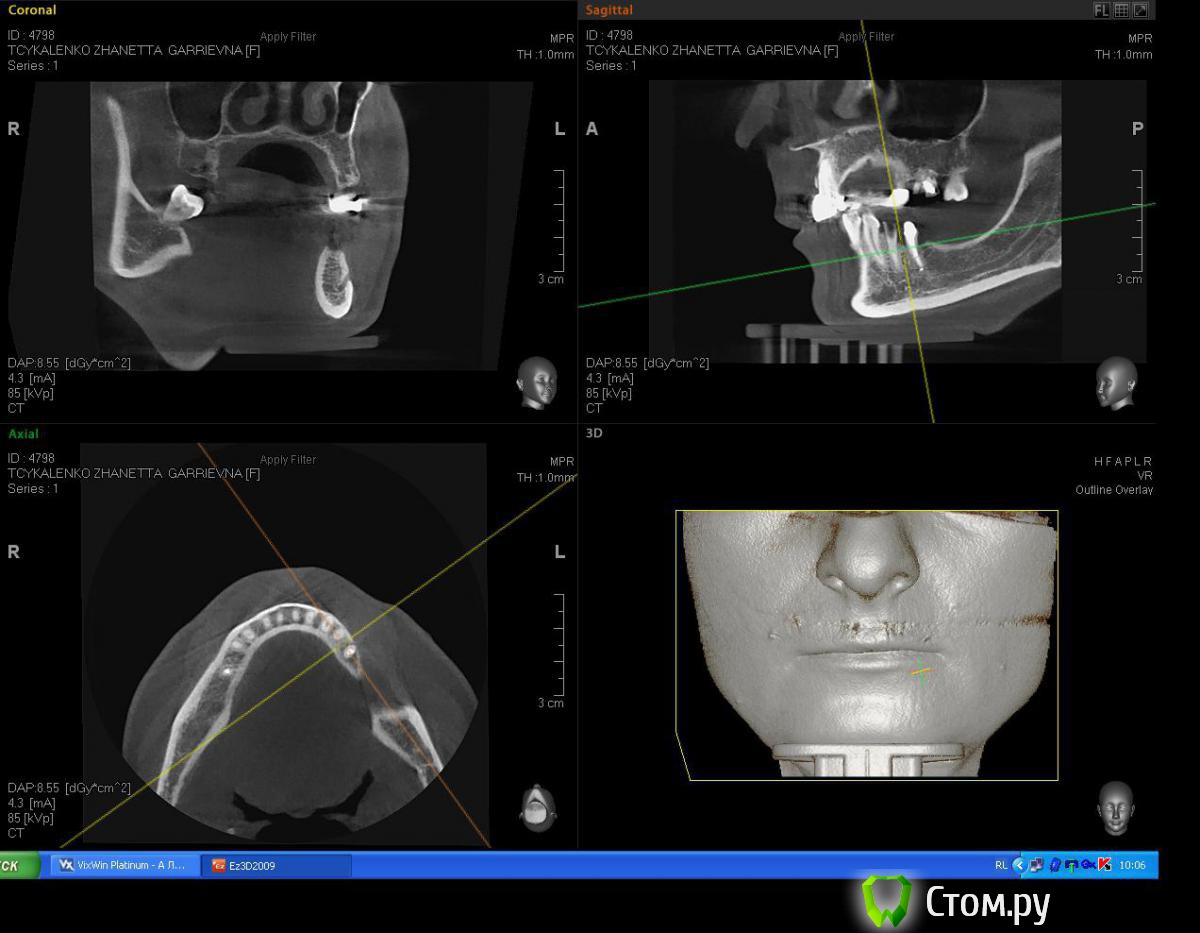

Mane Опубликовано 2 июля, 2014 Поделиться Опубликовано 2 июля, 2014 Для первичной фиксации вам неоходимо хотя бы 3-4 мм нативной кости в заапекальном направлении. Судя по срезам, они имеются, однако вместе со срезами лучше делать промеры (длина, ширина, толщина) для полноценной идентификации. Так же можете создать вируальный имплантат с планируемыми размерами и оценить его положение на срезах. +1 скорее всего вам будет достаточно 38х10 3 Ссылка на комментарий

Евгений Ходыкин Опубликовано 2 июля, 2014 Автор Поделиться Опубликовано 2 июля, 2014 Замеры по 3.4 зубу. Срезы с одним замером - это внутрикостная длина корня зуба. Ссылка на комментарий